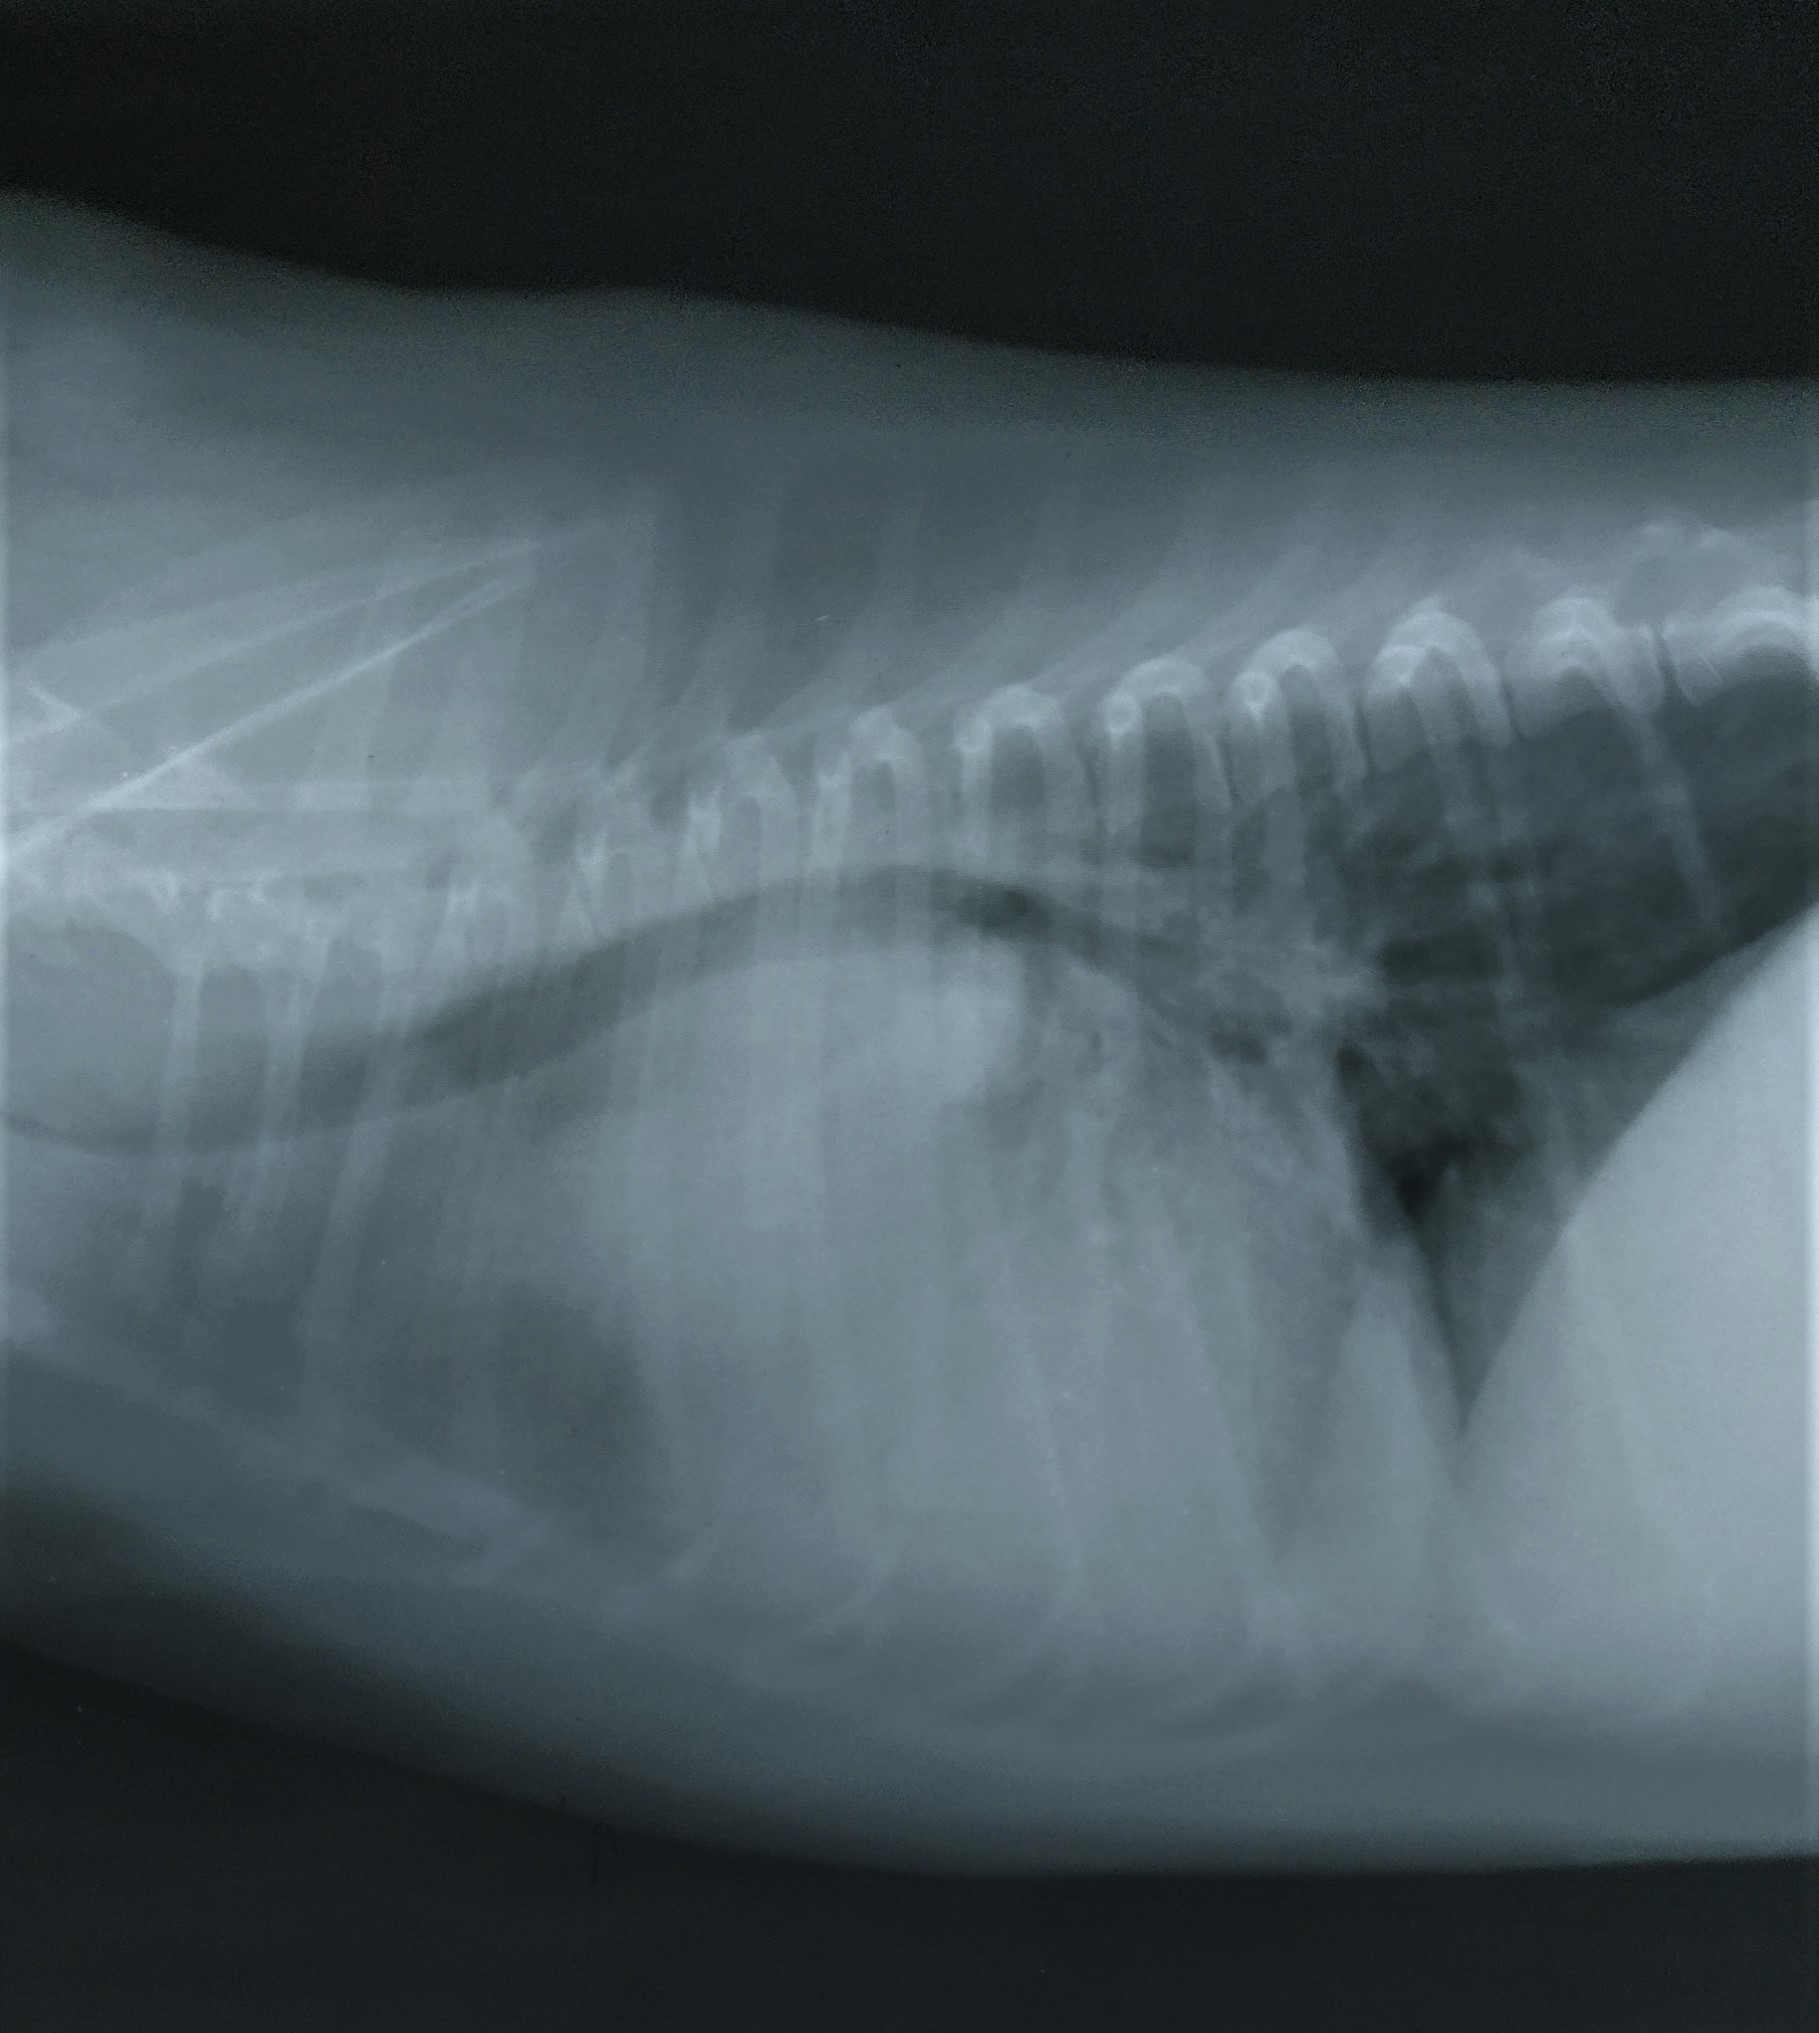

Pruebas realizadas por su veterinario y aportadas a DXIA.

Desplazamiento traquea cranealmente, perdiéndose el ángulo normal que debe tener con la columna. Cardiomegalia derecha sobre todo zona aurícula derecha o base cardíaca. Edema perihiliar leve.

Se observa estructura de densidad tejido blando que se superpone en zona de la silueta cardíaca, correspondiente a la zona de la aurícula derecha produciendo efecto silueta. Cardiomegalia. Aerofagia. Pulmón sin patrón alterado.